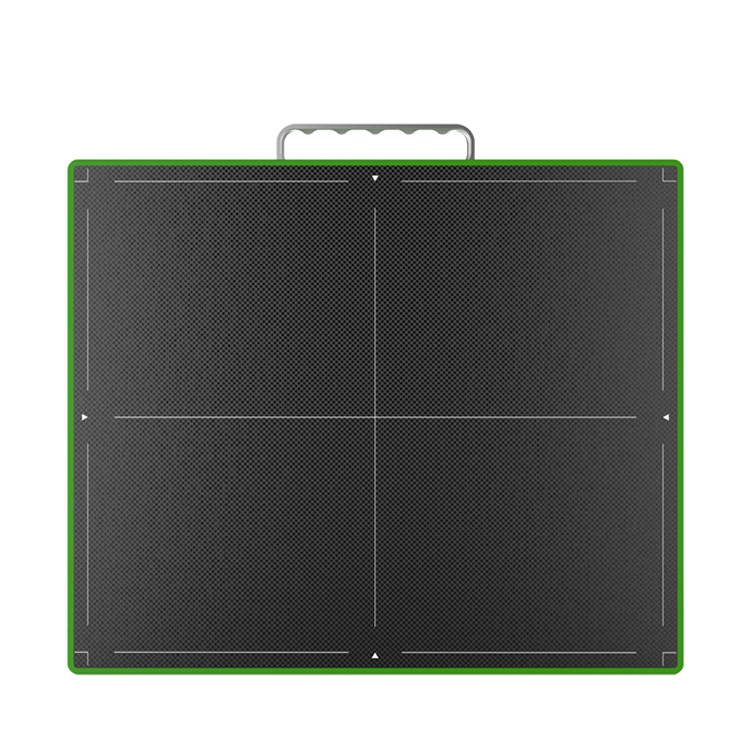

The MSLCV08 is a 17X17 box-type wireless portable flat panel detector designed for human digital radiography.

feature

- 1. Fast workflow

2. More image details

3. Excellent image quality

4. Cassette Flat Panel Detector